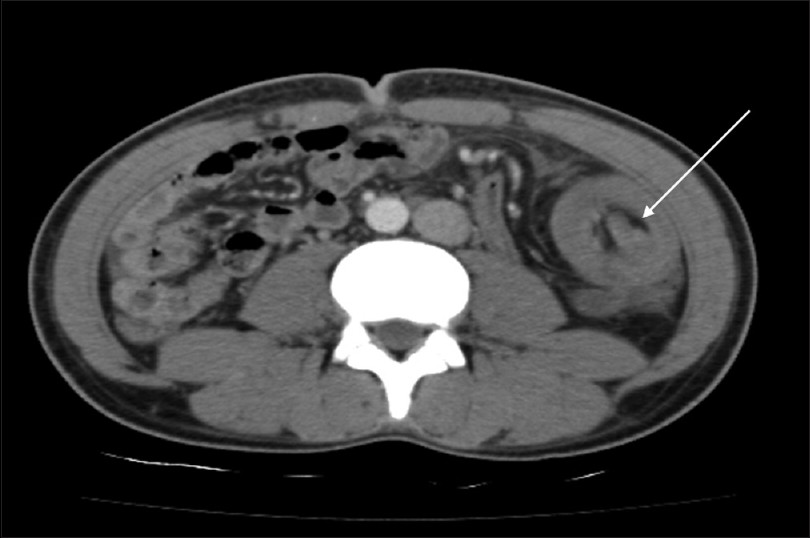

CT κοιλίας. Κόκκινο βέλος — Τυφλίτιδα. Σημαντική πάχυνση τοιχώματος τυφλού (Ευγενική παραχώρηση Dr. V. Penopoulos)